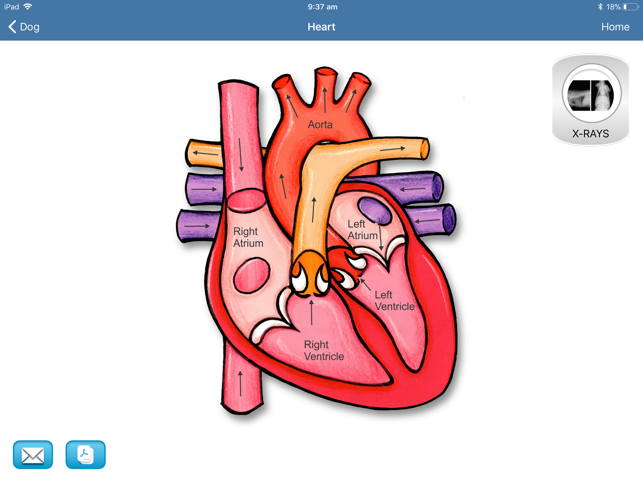

Increase value to your services

Are you still trying to explain a surgical procedure to your client using hand gestures or by stick drawings? Really? You want a client to say 'Yes' to a $3,000 TTA procedure with charades? With so much competition in the veterinary industry, you can't afford for a client to go for a second opinion or Dr Google themselves out of the procedure altogether. The iConsult will effectively and professionally help you educate your clients. There will be no need for Dr Google or second opinions.